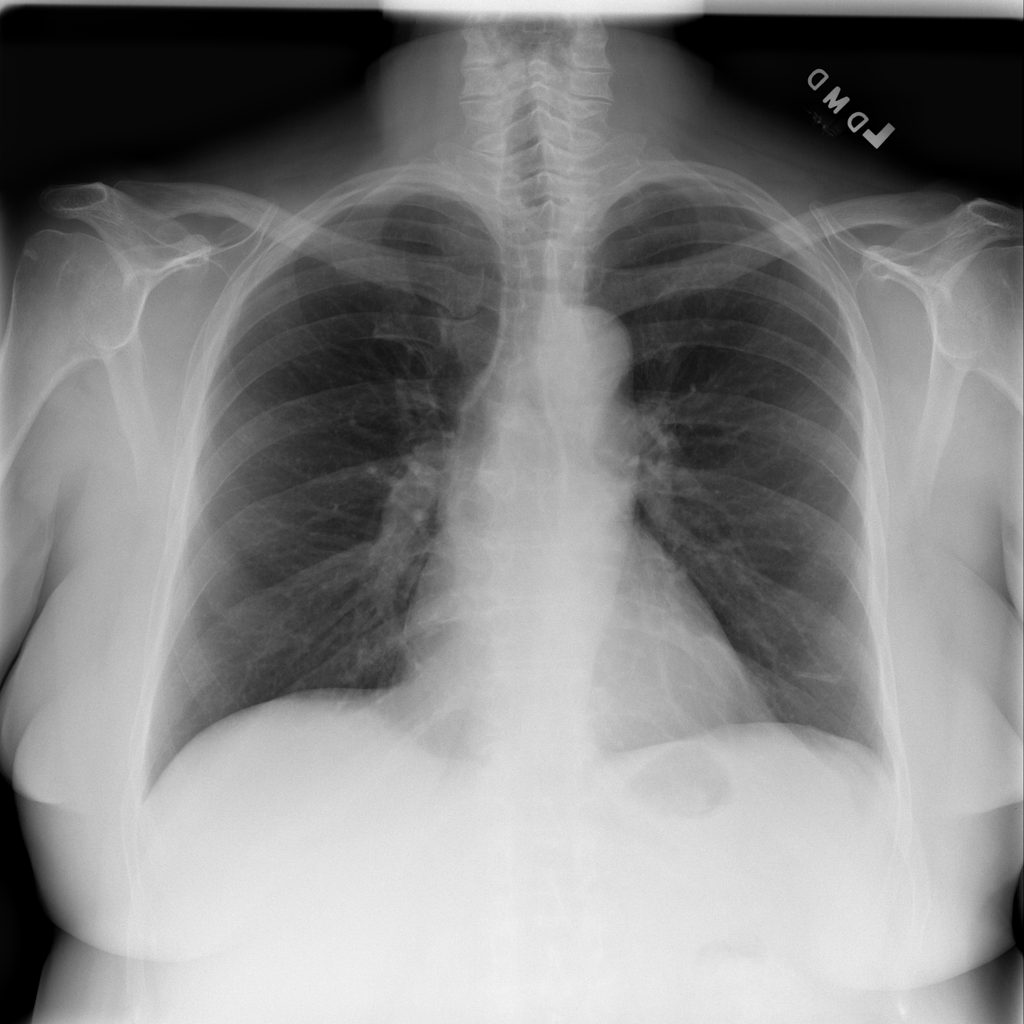

PAT-86C8 · IMG-006Atelectasis

PAT-86C8 · IMG-006

PA